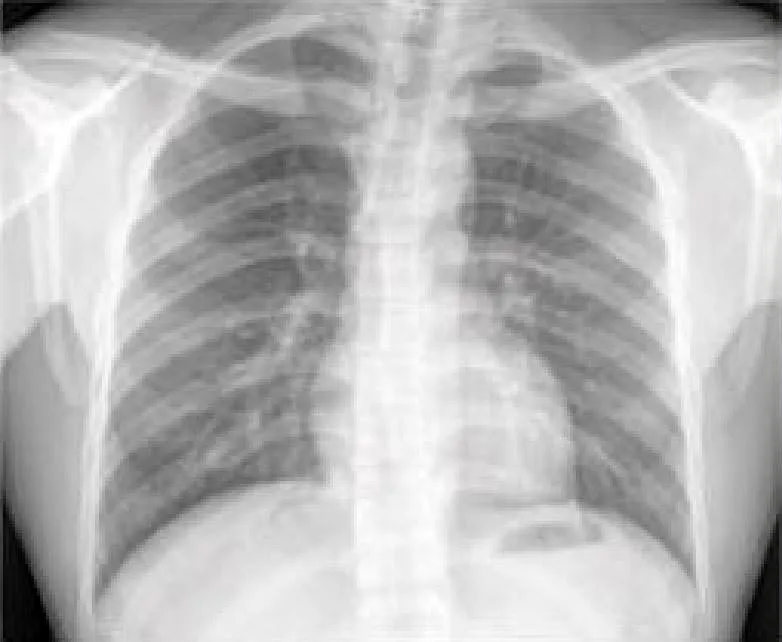

Weiss博士和一个研究小组使用单一的胸部X光(CXR)输入训练了一个深度学习模型。他们开发了这个被称为CXR-CVD风险的模型,利用前列腺癌、肺癌、结肠直肠癌和卵巢癌筛查试验中40643名参与者的147497张胸部X光片来预测心血管疾病的死亡风险,这是一项由美国国家癌症研究所设计和赞助的多中心、随机对照试验。

研究人员用第二个独立队列测试了该模型,该队列由11430名门诊病人(平均年龄60.1岁;42.9%为男性)组成,他们在麻省总医院布里格姆医院做了常规门诊胸透,并可能有资格接受他汀类药物治疗。

在11430名患者中,有1096人,或9.6%,在10.3年的中位随访期间遭遇了重大的不良心脏事件。CXR-CVD风险深度学习模型所预测的风险与观察到的主要心脏事件之间存在着显著的关联。

研究人员还将该模型的预后价值与决定他汀类药物资格的既定临床标准作了比较。由于电子记录中的数据(如血压、胆固醇)缺失,只有2401名患者(21%)可以计算出来。对于这部分患者,CXR-心血管风险模型的表现与既定的临床标准相似,甚至提供了增量价值。

"这种方法的好处是你只需要一张X光片,全世界每天可以产出上百万张,"Weiss博士说。"基于一个现有的胸部X光图像,我们的深度学习模型可以预测未来的主要不良心血管事件,其性能和增量价值与既定的临床标准相似。"